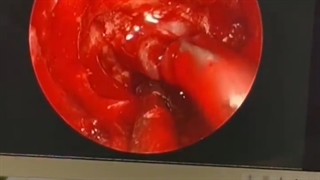

هیپوفیز

هیپوفیز، اولین تولید کننده ویدئوهای آموزشی اختصاصی علوم پزشکی!